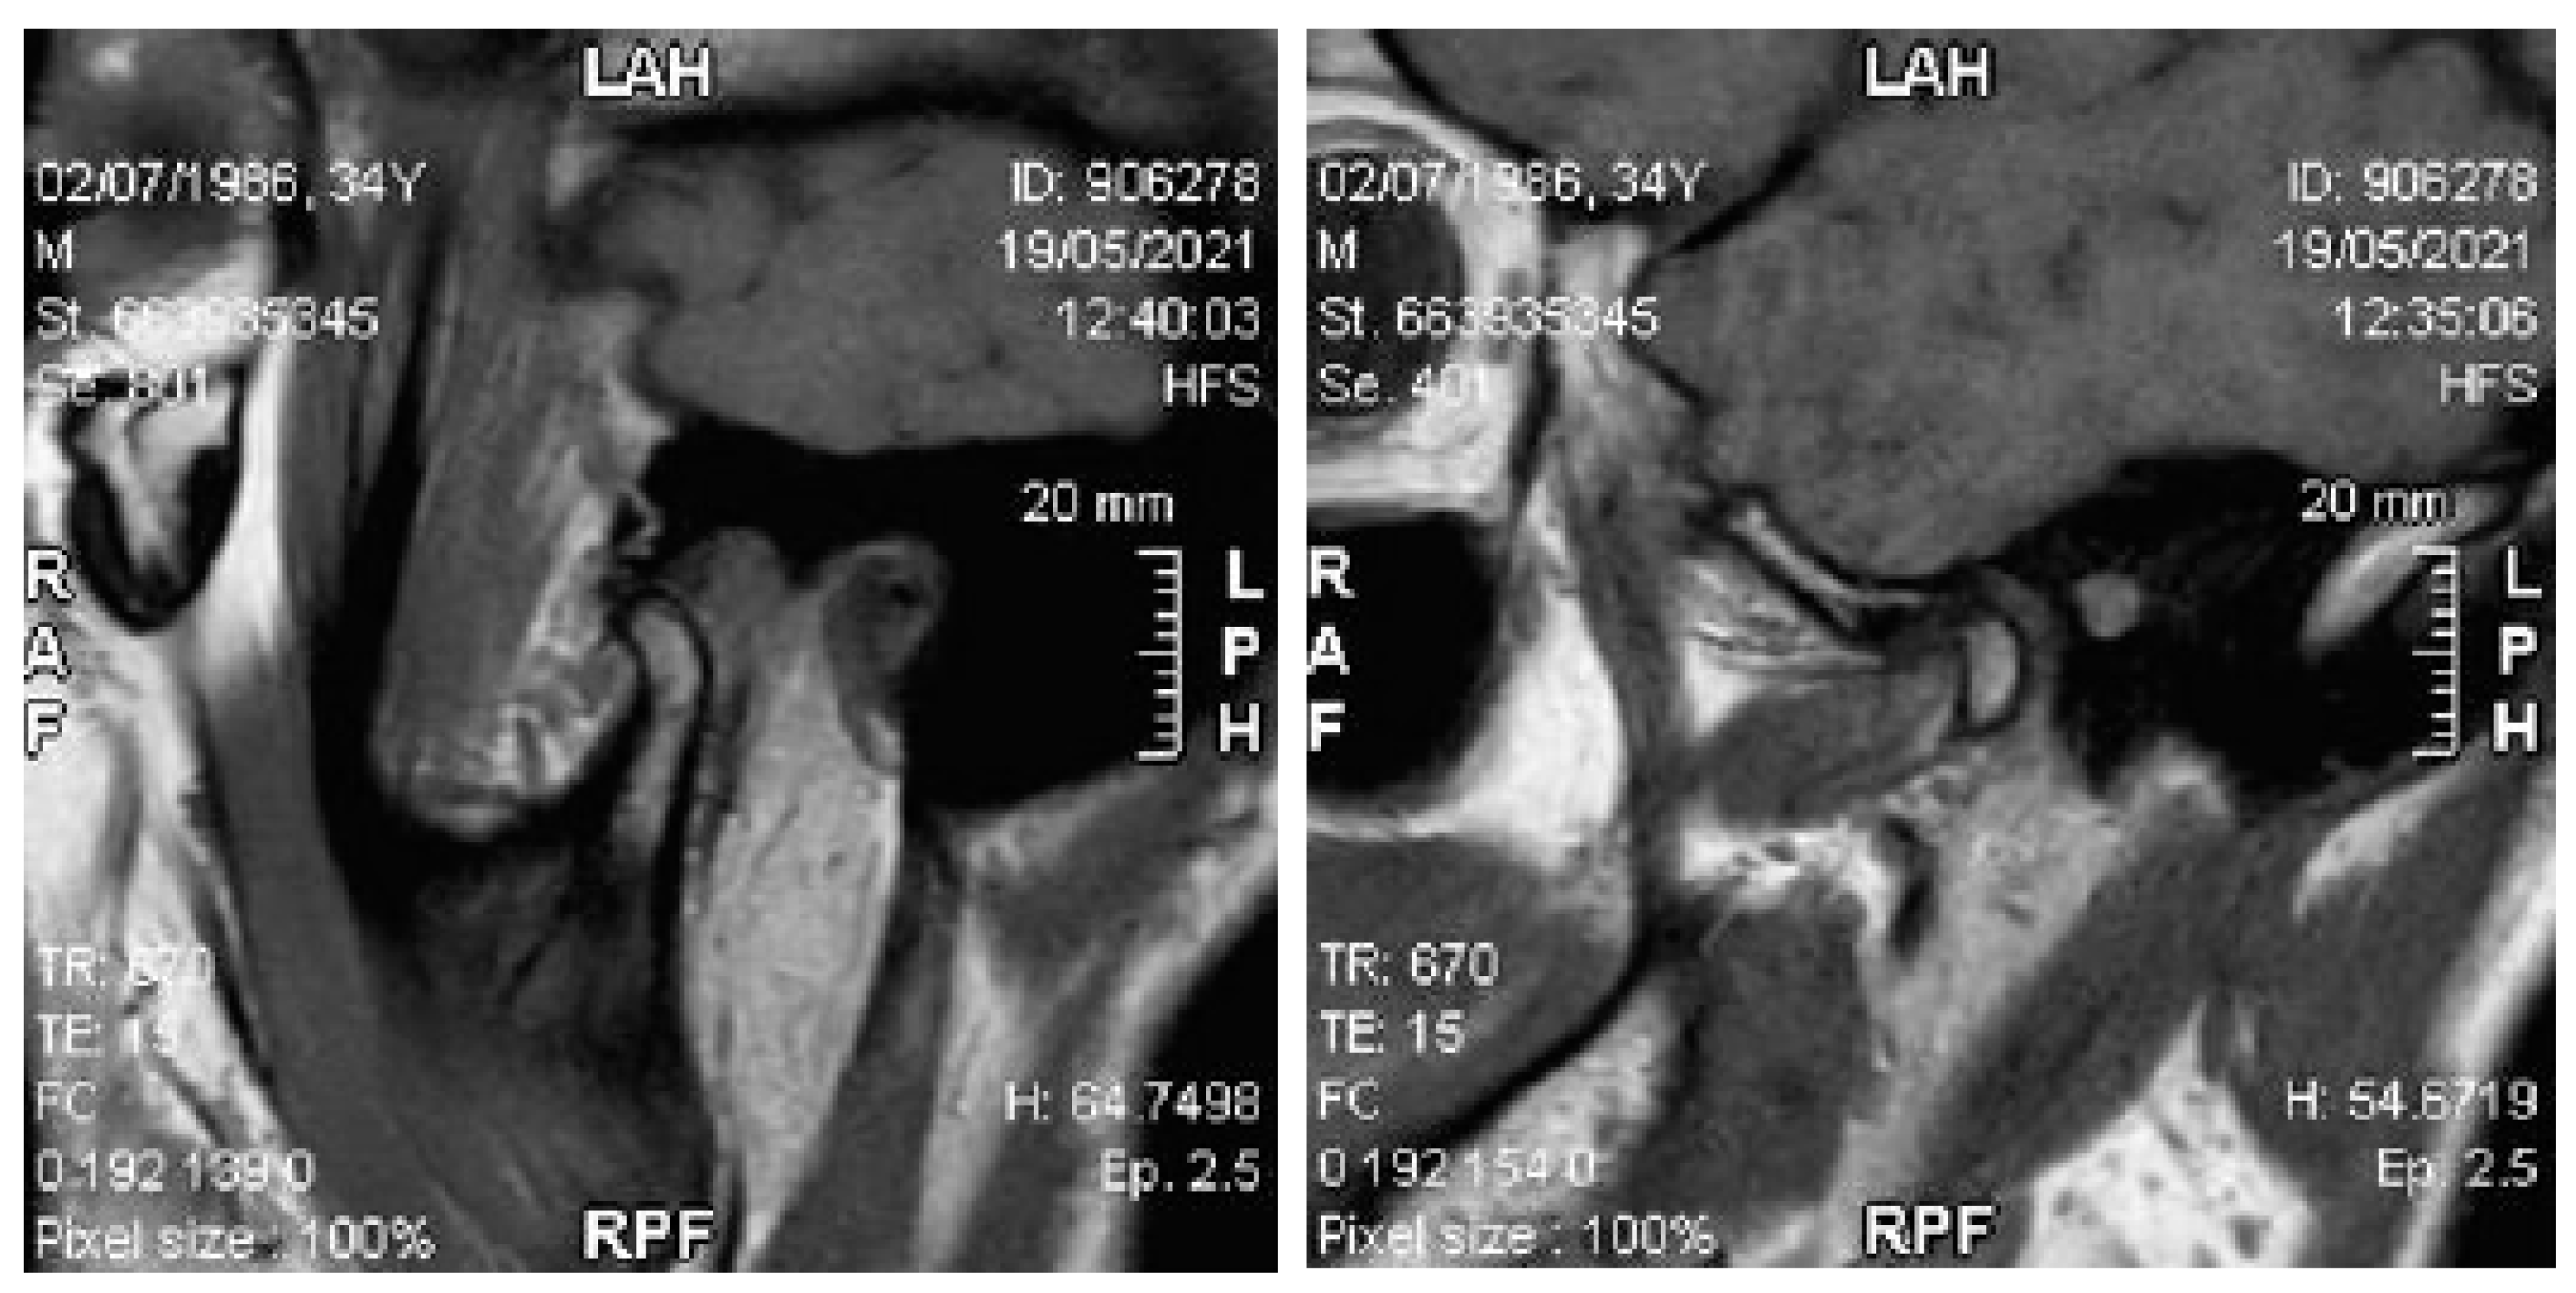

The patient showed a small opening width, approximately 25–30 mm, without pain. Lateral movements were within the norm. MRI images of the TMJ show anterior displacement of the disc with reduction (Figure 27).

Figure 27. MRI images with a closed and open mouth.